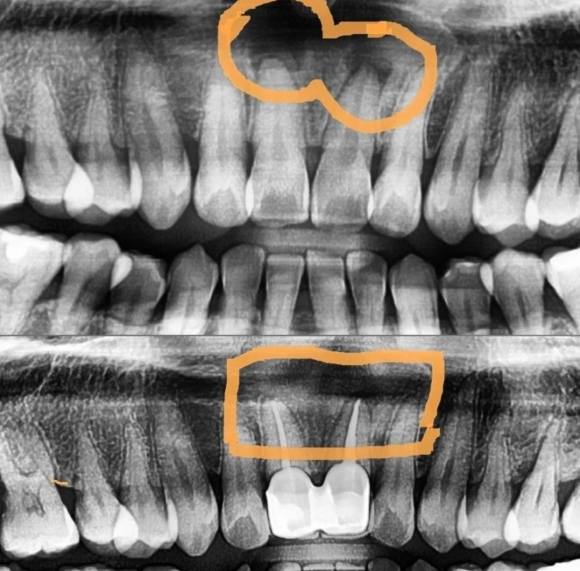

상기 환자 2021년 6월에 신경치료를 받았습니다. (위 사진 뿌리 끝 염증)

신경치료 1년 후, 염증이 사라지고 뼈로 가득찬 모습을 볼 수 있습니다 (아래 사진)

대부분의 뿌리 끝 염증은 신경관의 감염으로 인해 발생합니다.

사진 상 검게 보인 다는 것은 뼈의 소실이 매우 심했다는 것을 의미합니다.

치료가 늦을 수록 신경치료의 예후가 매우 떨어지니,

적절한 시기에 알맞은 치료가 매우 중요하다고 할 수 있습니다.

염증의 원인인 신경을 제거 하더라도,

이미 발생한 염증은 환자의 면역력에 의해 치유되기 때문에

환자의 면역 요소도 매우 중요하다고 할 수 있습니다.

나이가 많을 수록 신경치료의 성공율이 떨어지는 이유이기도 합니다.